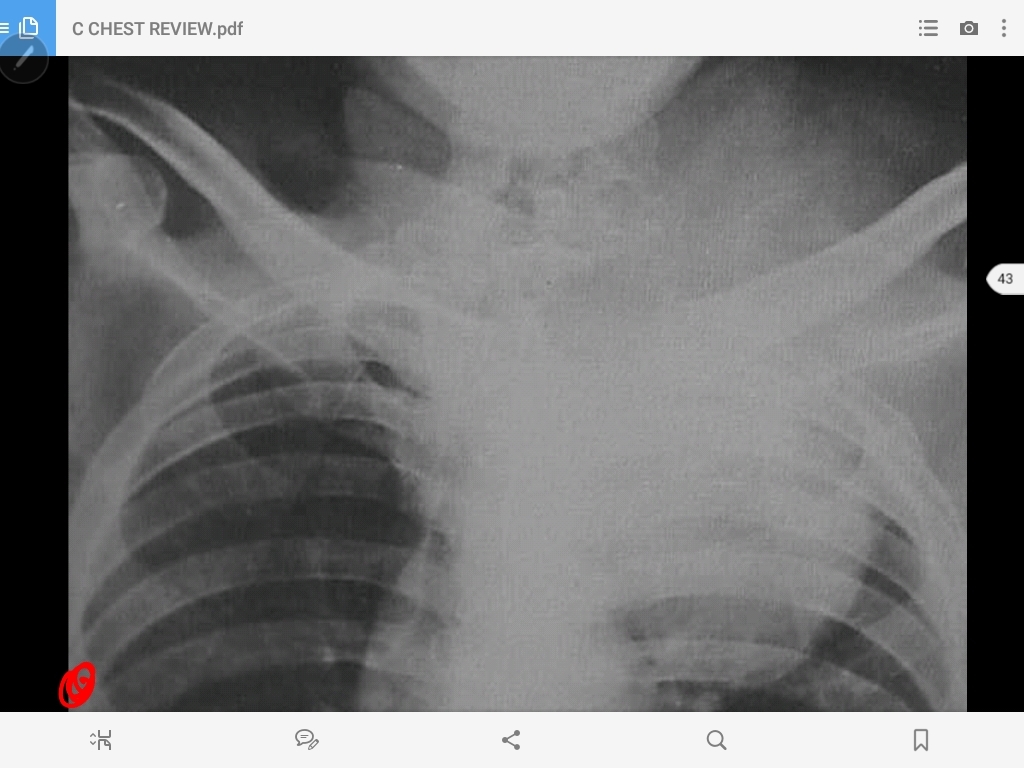

pancoast tumor